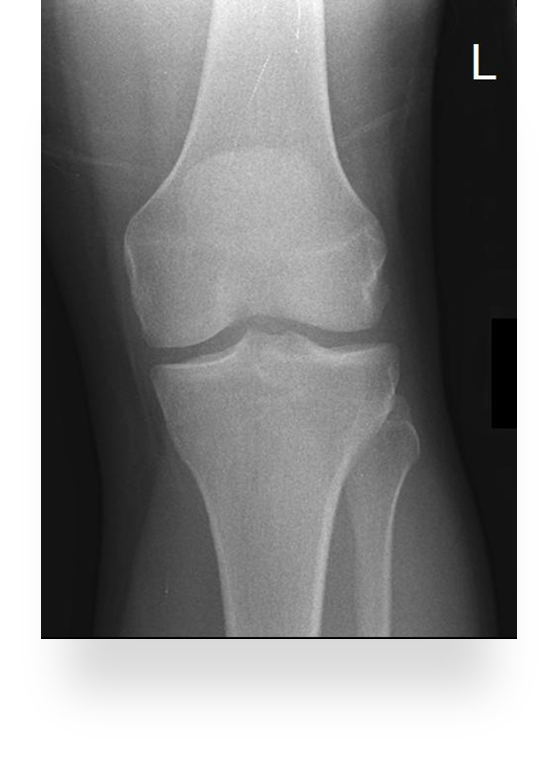

Trauma and Non Trauma AP Knee

•Evidence of proper collimation and the presence of a side marker placed clear of the anatomy of interest

•Knee fully extended if patient’s condition permits

•Entire knee without rotation

•Femoral condyles symmetric and tibia intercondylar eminence centered

•Slight superimposition of the fibular head if the tibia is normal

•Patella completely superimposed on the femur

•Open femorotibial joint space, with interspaces of equal width on both sides if the knee is normal

•Bony trabecular detail and surrounding soft tissues

Patella is in the center! good! equal distance of joint space/platoes which is good

ACCEPTABLE BECAUSE EVERYTHING ELSE IS GOOD! PATIENT COULD HAVE A MORE SEPARATED FIBULAR HEAD! THEIR ANATOMY IS DIFFERENT. CENTERING IS GOOD